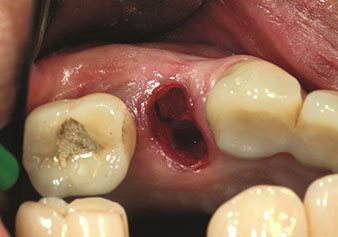

Une application souvent sous-estimée est l’extraction atraumatique de racines dentaires ou de fragments radiculaires dans le cadre d’une gestion alvéolaire. Les périotomes à denture fine, qui sont actuellement disponibles en deux versions (EX1 et EX2 de W&H), peuvent également être utilisés pour extraire facilement des dents qui ont subi un traitement endodontique spécifique préalable ou des racines ankylosées. On obtient des alvéoles d’extraction dans lesquelles à la fois les tissus durs et les tissus mous sont entièrement préservés.

Ceci instaure des conditions optimales pour un traitement implantaire ultérieur ou immédiat (Figures 1 et 2 fournies avec l'autorisation du Dr Torsten Conrad, Bingen

am Rhein).